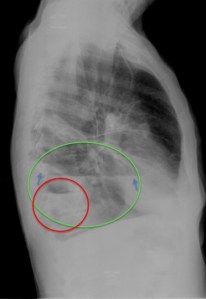

En la placa PA, se observa un encapsulado pleural (verde) y una cavidad parenquimatosa (roo), ambas con nivel hidroaéreo. En el pleural, obsérvese la discordancia del nivel (flechas), tanto en longitud como en densidad, entre las dos proyecciones y borramiento de la pared superior y más posterior en la placa lateral. En la cavidad parénquimatosa, se conserva la misma forma y densidad en las dos proyecciones, con delimitación del controno superior de su pared.

Esquema 1. Sección Transversal de tórax en la que se representa la configuarción lenticular del encapsulado pleural en localización posterior (1) y (2) y la morfología redondeada que adopta una lesión intrapulmonar (3). Un nivel hidroaéreo en (1) y (2) mostrará una discordancia en tre sus dimensiones en P.A y lateral. En (3) el nivel será igual en cualequiera de las dos proyecciones.

Esquema 2. Sección sagital de tórax en la que se representa un encapsulado pleural posterior y una lsesion parenquimatosa con nivel hidroaéreo. El afilamiento periférico del encapsulado determina la ausencia draiológica de su pared superior en al menos una de las proyecciones. En la lesión parenquimatosa, la pared es visible al estar rodeada por aire.